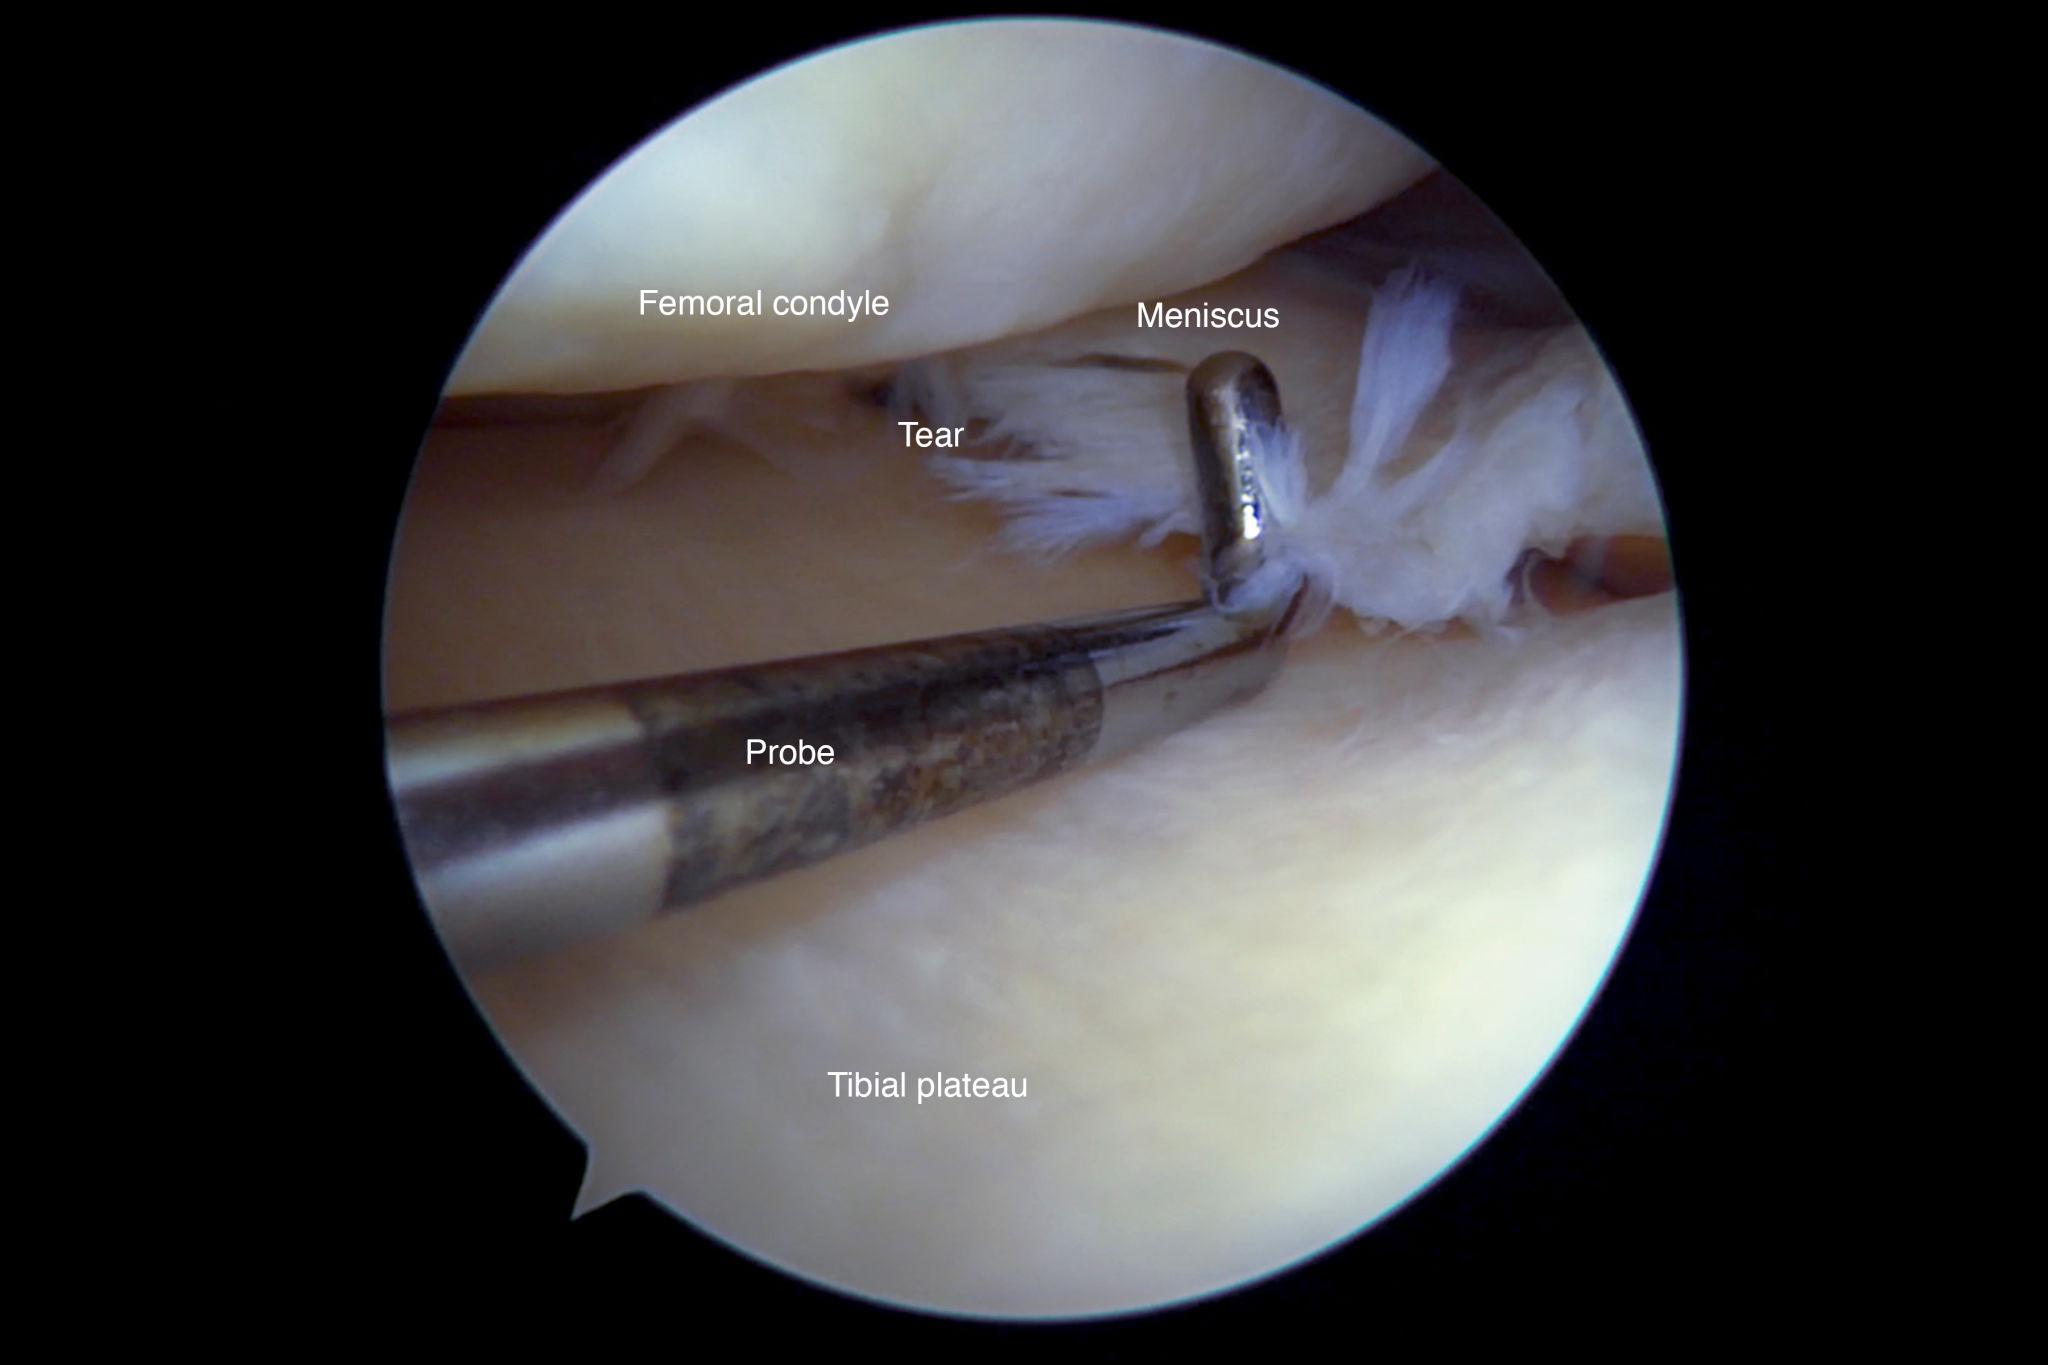

ACL (Anterior Cruciate Ligament) tear

Meniscus tear

At Inova Hospital, we specialize in arthroscopic (keyhole) surgery, which offers:

Procedures include: